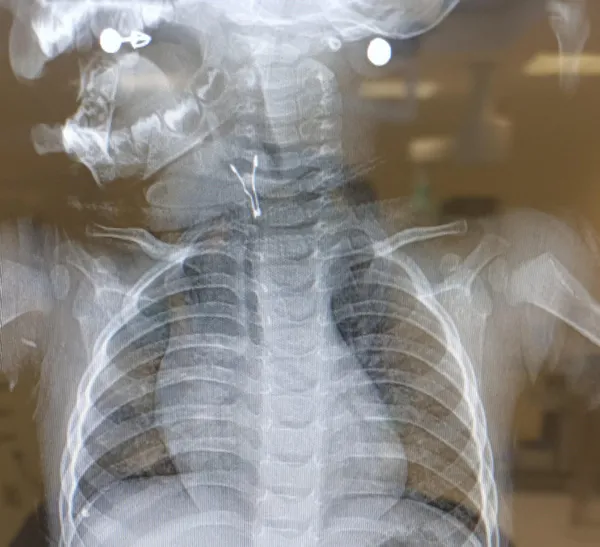

Solunum yoluna yabancı cisim kaçan çocukların genellikle ciddi solunum sıkıntısıyla hastaneye getirildiğini kaydeden Opr. Dr. Mehmet Çakmak, "Bazı gecikmiş olgularda nedeni bulunamayan kronik öksürük şikayeti oluyor. Bazen 1 ay sonra bile o yabancı cisim bir röntgende farkedilip bize gönderilen hastalar olabiliyor. Röntgende de görülmeyebiliyor bazı çisimler. Radyoopak madde olması gerekiyor röntgende görünebilmesi için." diye konuştu.

Ailelerin, çocuk özellikle ek gıdaya geçtikten sonra ağızlarına götürdükleri cisimlere çok dikkat etmeleri gerektiğini belirten Dr. Çakmak, sözlerini şöyle sürdürdü: "Çocuk tadına bakmak için ya da keşfetmek için ne bulursa ağzına götürebiliyor. 2 yaşından sonra kuruyemiş tarzı gıdalar aileler tarafından çocuğa istemli bir şekilde verilebiliyor mesela. Bunlar da çocukta çiğneme alışkanlığı tam olarak kazanılmamışsa, soluk borusuna kaçabiliyor. Yabancı cisim yutmada en sık, evin içerisinde kolay ulaşılabilen şeylerden biri olan bozuk para yutmayla karşılaşıyoruz. Genellikle yemek borusunun birinci darlığında tıkanma yapıyor metal para. Bu tür hastalar zaten tükürüklerini dahi yutamıyorlar, beslenemiyorlar, bu şikayetle bize getiriliyorlar. Biz kolay ulaşılabilir bir bölgede olduğu için beslenme yolundan parayı rahatlıkla çıkarabiliyoruz. Ama mideye düşen ya da bağırsağa geçen yabancı cisimlerde herhangi bir müdahale yapmıyoruz. Bekle gör politikasını uyguluyoruz. Çünkü gastrointestinal sistemin yani ağızdan anüse kadar olan sindirim sisteminin en dar bölgesi yemek borusunun birinci darlığı. Buradan geçen her cisim, dışkı ile atılabilir."